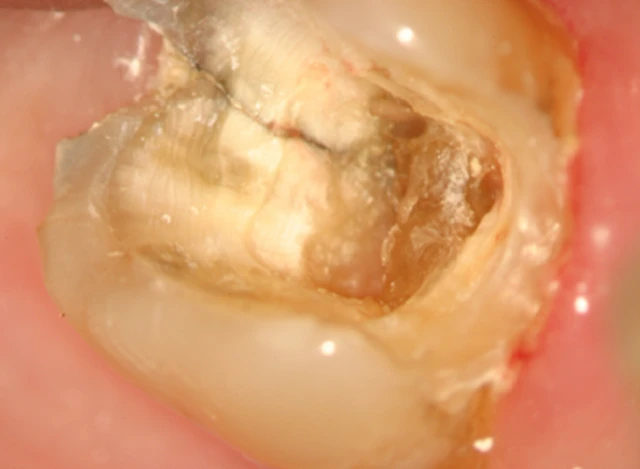

Phương pháp chiếu sáng và dùng thuốc nhuộm

Đôi khi cần phải tháo miếng trám trên răng để có thể quan sát vết nứt rõ hơn. Nhuộm bằng Xanh Methylene bằng cách bôi thuốc lên bề mặt răng bằng đầu tăm bông, thuốc nhuộm sẽ quyên qua vùng nứt và xác định vị trí đường nứt. Chiếu sáng cũng có thể hữu ích hơn bằng cách chiếu trực tiếp ánh sáng có cường độ cao vào bề mặt răng tại đường nối men – xi măng để xem mức độ lan rộng của vết nứt. Phần răng gần với nguồn sáng sẽ hấp thu ánh sáng và phát sáng, trong khi phần răng phía bên kia của vết nứt không được sánh sáng truyền qua sẽ có màu xám hơn. Mặc dù có thể phát hiện được vết nứt bằng thuốc nhuộm hoặc ánh sáng nhưng độ sâu của vết nứt không thể lúc nào cũng xác định được.

Phương pháp chiếu sáng và dùng thuốc nhuộm